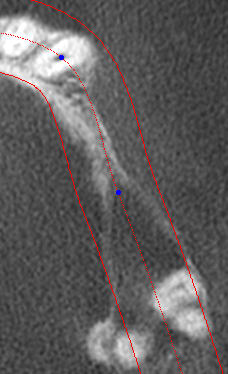

voici un cas typique de résorbtion GARANTIE d'un bloc allogène.

Si vous regardez bien le scan pré-op , la résorbtion est palatine et la greffe d'apposition est vestibulaire.

Alors où est l'erreur ??

Les implants sont posés dans le bloc , et on voit bien à la photo post-op que les implants sont vestibulés par rapport aux dents mésiales.

Carlo Tinti l'a montré à plusieurs repises: une greffe en dehors du volume physiologique ne peut que disparaitre.

L'essentiel n'est pas de réussir une prouesse chirurgicale, c'est de garantir la stabilité à long terme. Et dans ce cas là, je ne suis pas du tout optimiste. A ressortir dans 1 ou 2 ans

En comparant sur le scanner le site de greffe avec le site de la dent qui est juste avant on se rend compte effectivement que la perte osseuse est bien vestibulaire.